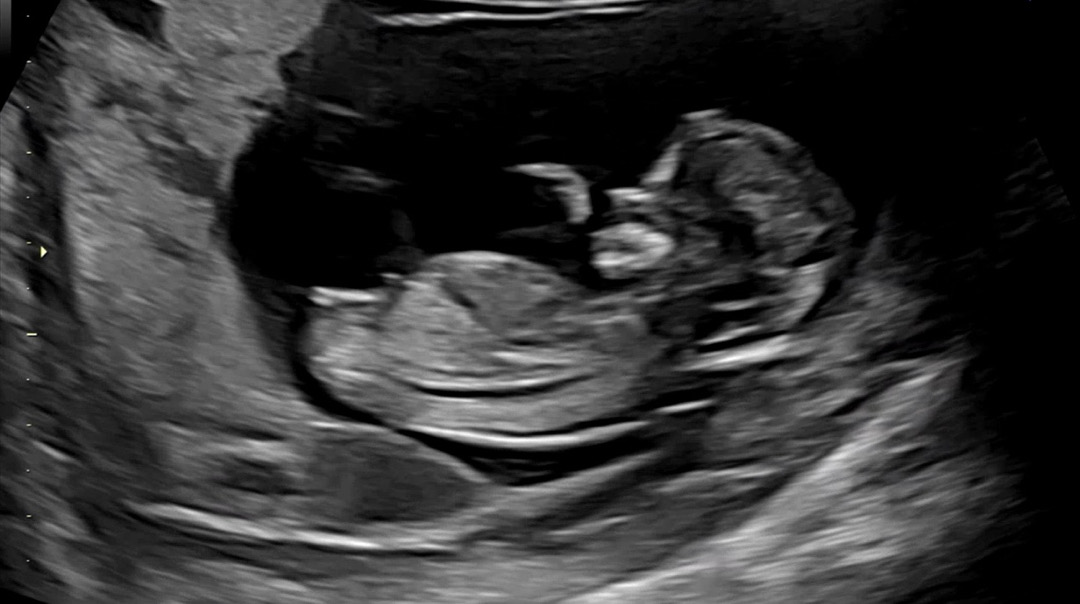

12주4일 각도법 성별 투표부탁드립니다🍀!!!

12주4일 초음파 봤는데 아직 성별은 알 수 없다고 하셔서요😭 너무너무 궁금해서 처음 올려봅니다 :) 각도법이 뭔지.. 초산이라 제 눈엔 잘 모르겠어요 ㅠㅠ 투표 부탁드려요 ⭐️